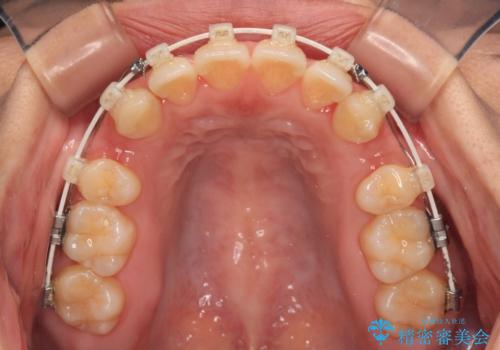

- 矯正装置

- 審美装置

- 全体的なデコボコと口元の突出感を改善したいとのことで来院された患者様です。

このままデコボコを整えるとさらに突出感が増すため、上下左右の第一小臼歯を抜歯し、ワイヤー装置にて矯正しました。

結婚式で途中装置を外した時期がありましたが、2年で治療を終えることができました。